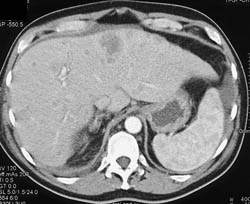

Liver Metastases